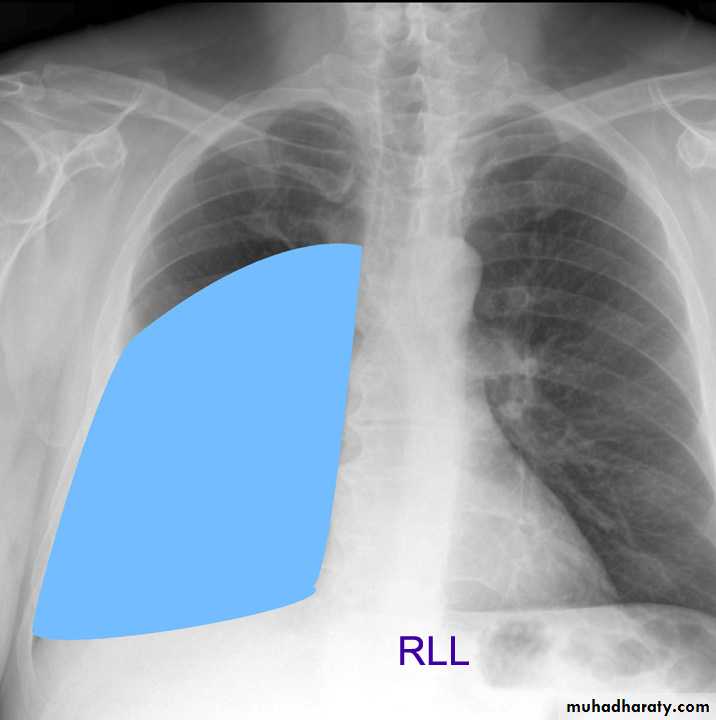

Lung Anatomy

Zonal anatomyLobar anatomy

Rt lung divided to 3 lobes (upper , middle & lower )

Transverse fissure separate the upper lobe from middle lobeOblique fissure separates the upper & middle from lower lobe .

The left lung subdivided to two lobes by oblique fissure ( upper & lower )

Rt upper lobe

Rt middle lobe

Rt lower lobe

Left upper lobe

LUL collapse

Left lingula

Left lower lobe